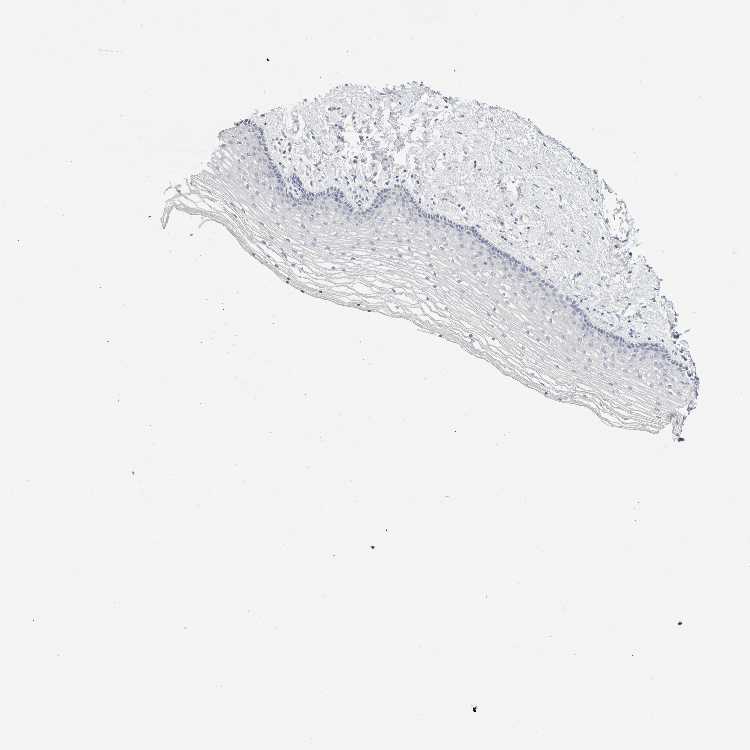

VAGINA - Antibody stainingi

Antibody staining in the annotated cell types in the current human tissue is reported as not detected, low, medium, or high, based on conventional immunohistochemistry profiling in selected tissues. This score is based on the combination of the staining intensity and fraction of stained cells.

Each image is clickable and will lead to virtual microscopy that enables deeper exploration of all samples and also displays staining intensity scores, fraction scores and subcellular localization as well as patient and tissue information for each sample.

Antibody HPA007865Antibody CAB025862

Squamous epithelial cells Not detectedNot detected